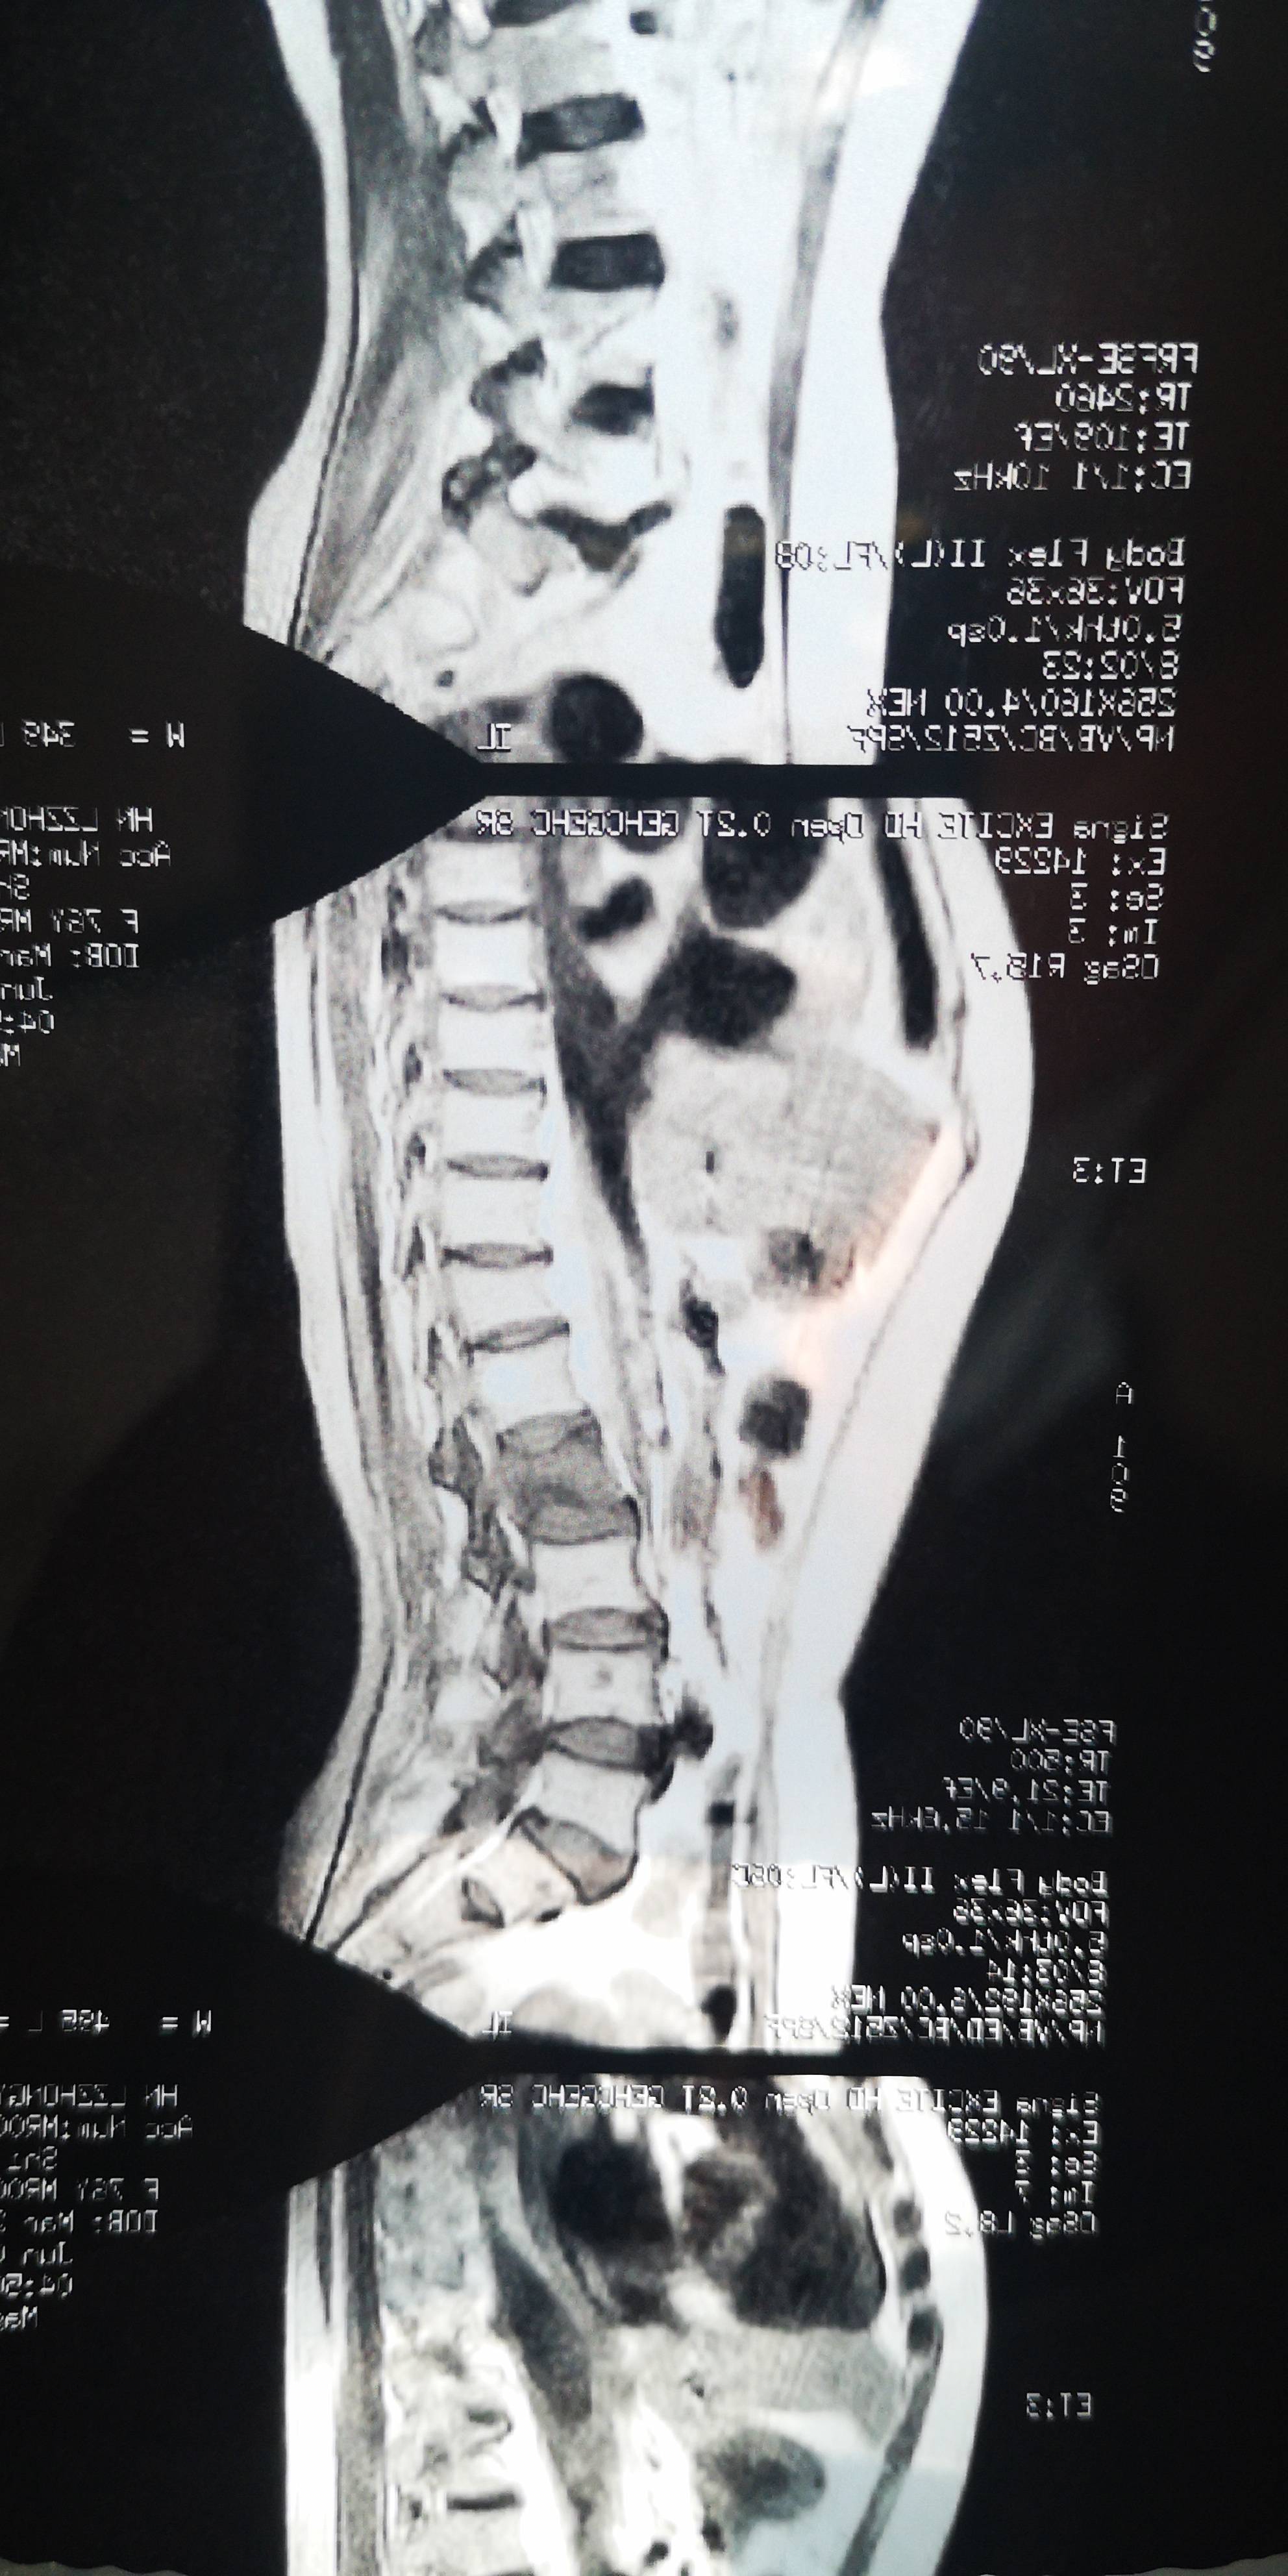

2021年6月6日腰部磁共振显示,腰椎二骨转移严重(由于3月份的头颈胸腹未提示腰椎骨转移,所以我猜是放疗期间发生转移的)。随双氯芬酸钠栓24小时一粒,病人方得安宁。